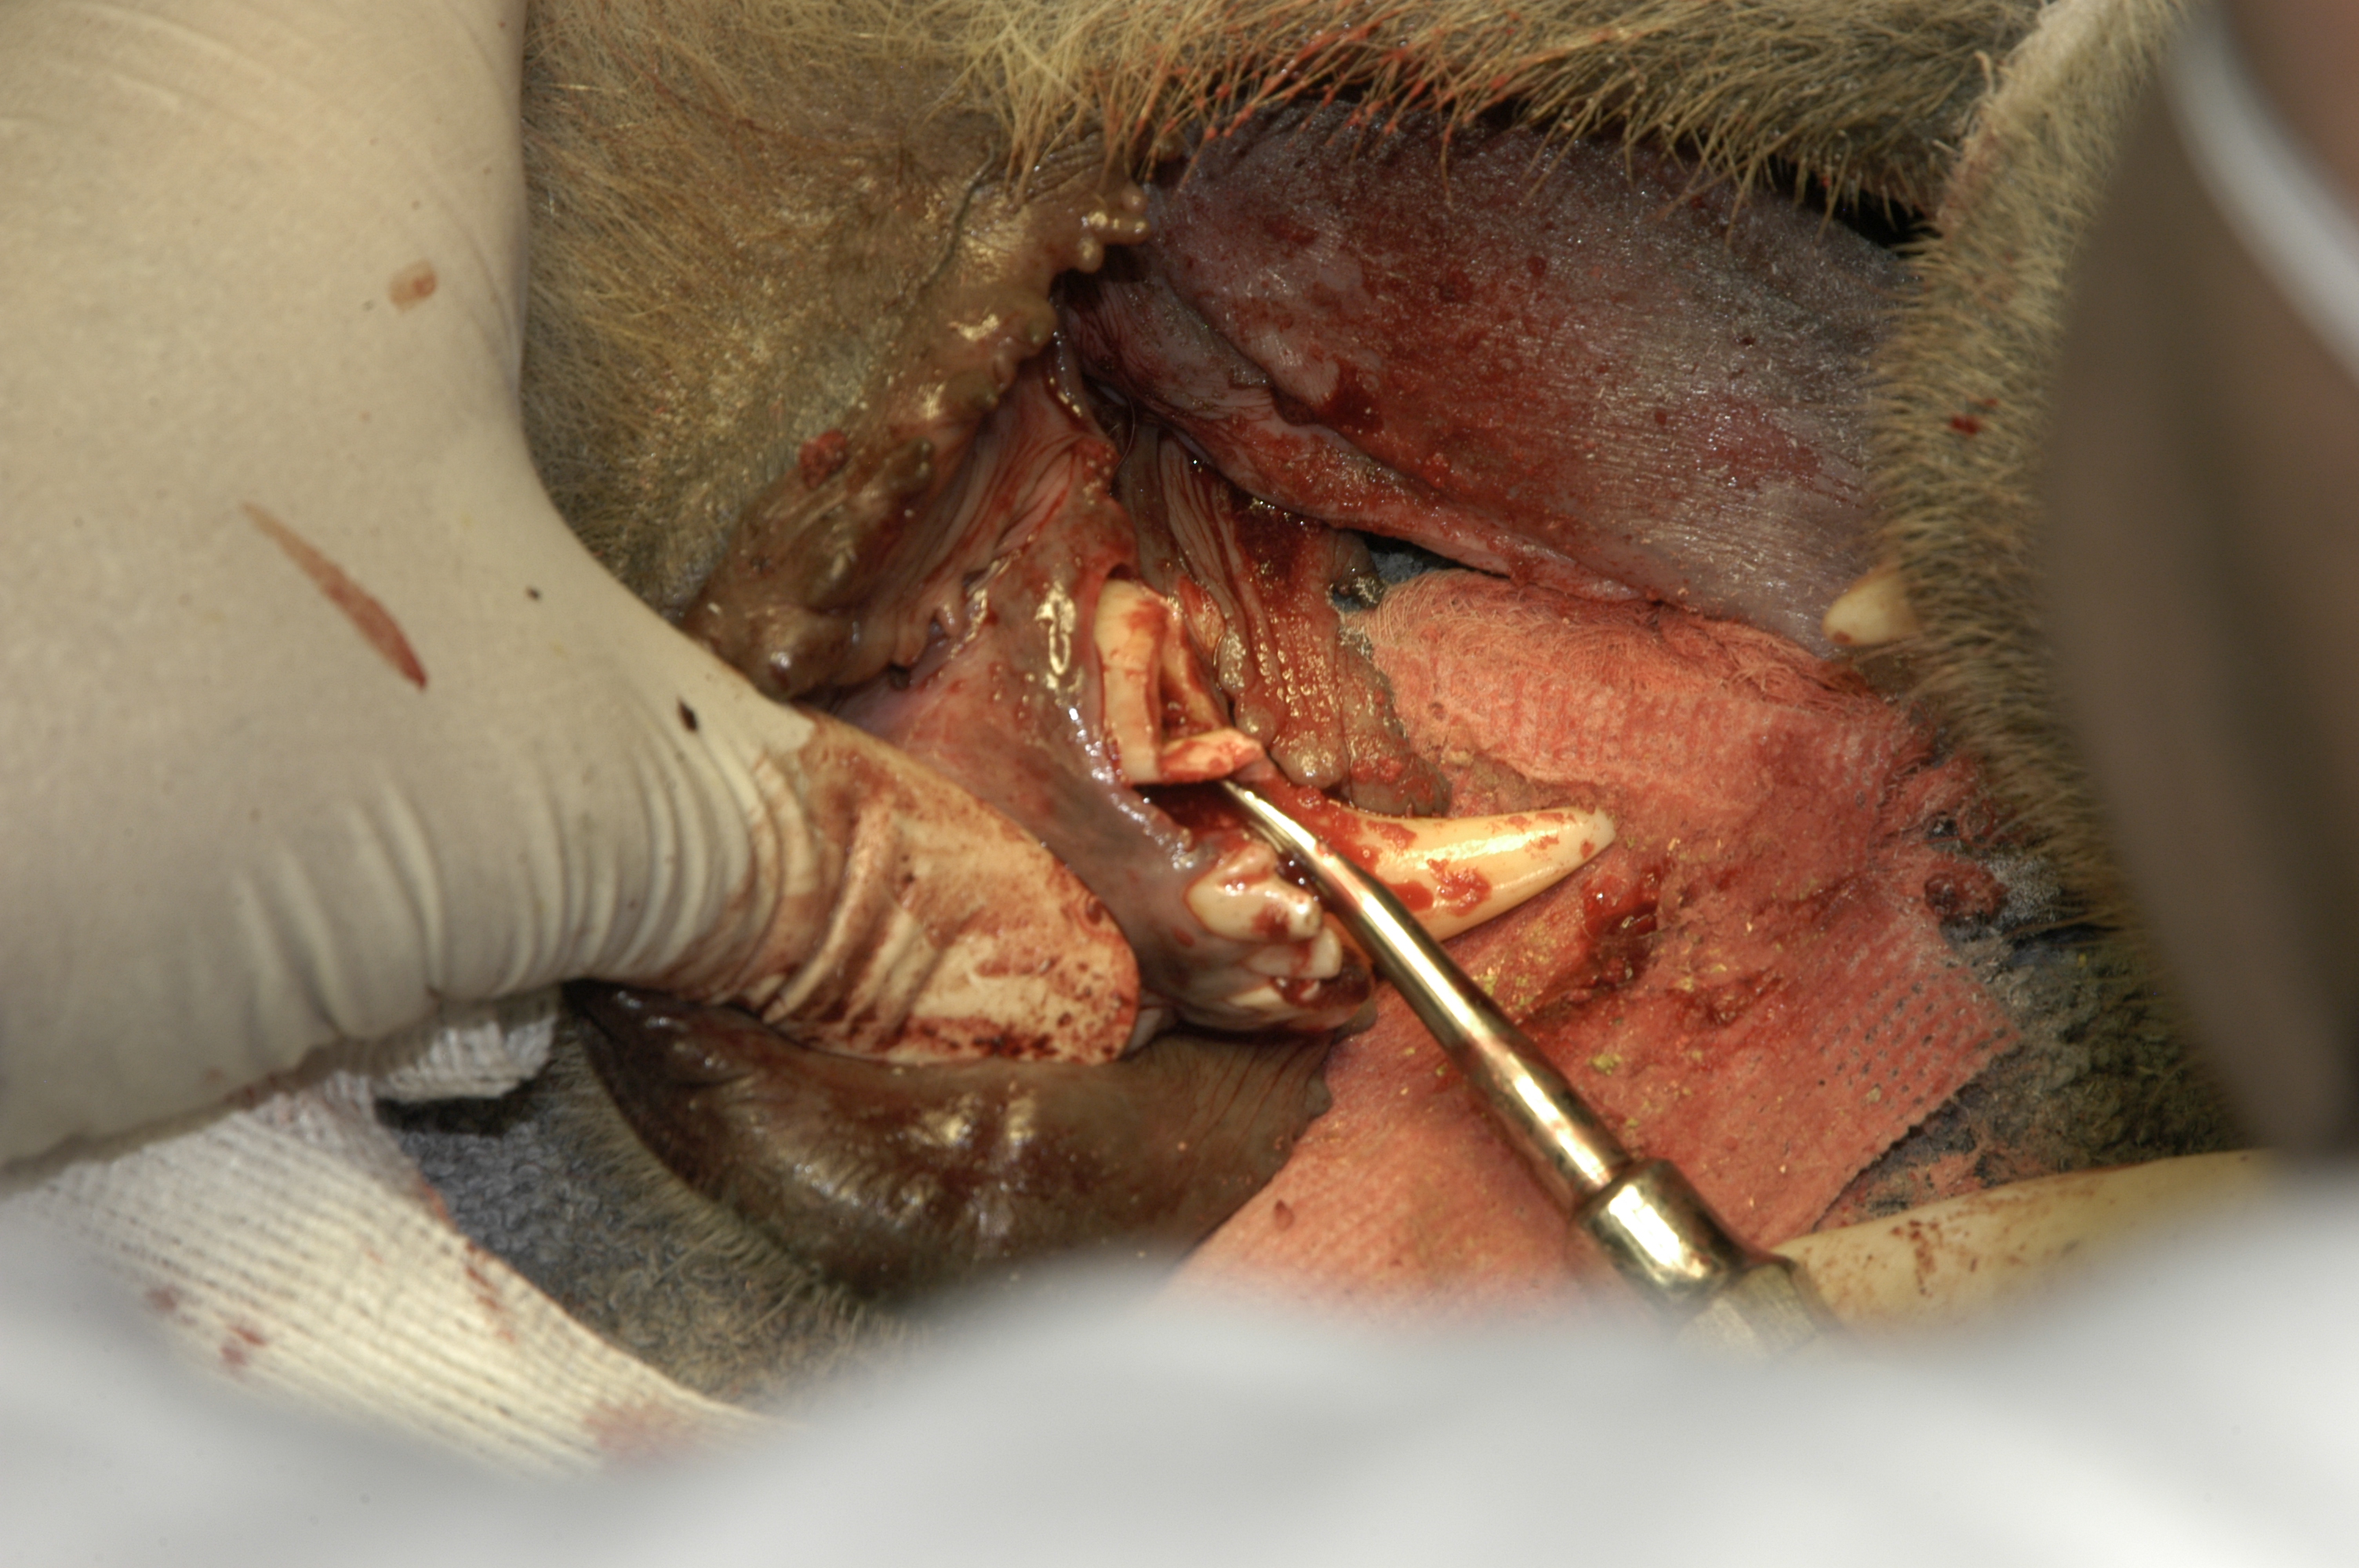

July, 1987Milwaukee County Zoo.Bongo female, “Ira” fractured her mandible through the cartilaginous symphysis when she panicked and ran into an enclosure wall. She had done this before, fracturing her mandibular incisors, which had been observed by her keepers. However, she had not been sedated for an exam by the veterinarians, in great part because of her skittish nature.

When she was anesthetized the night of this severe injury, July 4, 1987, it was apparent that the anterior segment of her mandible was infected because of the multiple fractured incisors and the infected bone had become severely weakened. Fortunately, the posterior segment of the cartilaginous symphisis was intact and still held the right and left mandible bodies connected. Zoo veterinarian, Dr. Bruce Beehler anesthetized “Ira” and we examined the fracture. With the help of a large animal veterinarian I used ligature wire to lift up the anterior segment, securing it to the still intact mandible symphisis. We understood that this was just a temporary fix. Soon after “Ira” was awake she began to feed and put downward pressure on the repair.

I enlisted the aid of veterinary surgeon Dr. Paul Howard from the University of Wisconsin School of Veterinary Medicine. He came to Milwaukee County Zoo the next evening, July 5, with a surgical assistant and appropriate orthopedic equipment. After removing the ligature wire repair and debriding the wound he reduced the fracture securing it with six intermedullary pins. Extensive suturing was necessary to repair the damaged tissues. The pins held the reduction.

Over time some of the pins loosened and came out. However, the reduction held and the mandible healed in place with modest malposition and a slightly drooping lip. “Ira” lived for several years and had healthy calves.

Bongo “Ira” mandible symphysis fracture presentation.